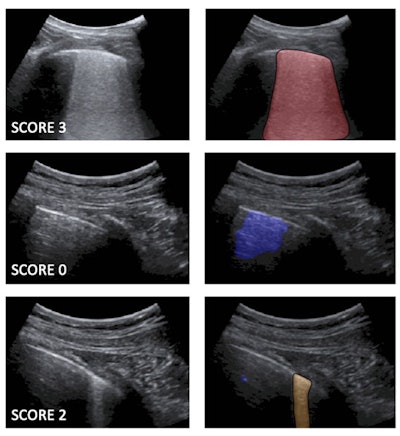

Following up on prior work to develop standard lung ultrasound protocols and training deep-learning algorithms for COVID-19 patients, the researchers wanted to compare the performance of their models with that of expert clinicians. The first algorithm labels each video frame with a score, while the second provides semantic segmentation -- assigning one or more scores to each frame.

The algorithm's scores for each frame are then used to generate an aggregate score for each video. The researchers tested two methods for producing an aggregate score: one based only on the labeled video frames and another that combined the labeled frames with the segmented frames.

"Therefore, the first approach can be considered as a self-standing strategy to classify [lung ultrasound] videos starting from a frame-based classification," the authors wrote. "Nevertheless, the semantic segmentation remains essential for clinicians, as it provides the explainability of the decision by highlighting the specific [lung ultrasound] patterns."